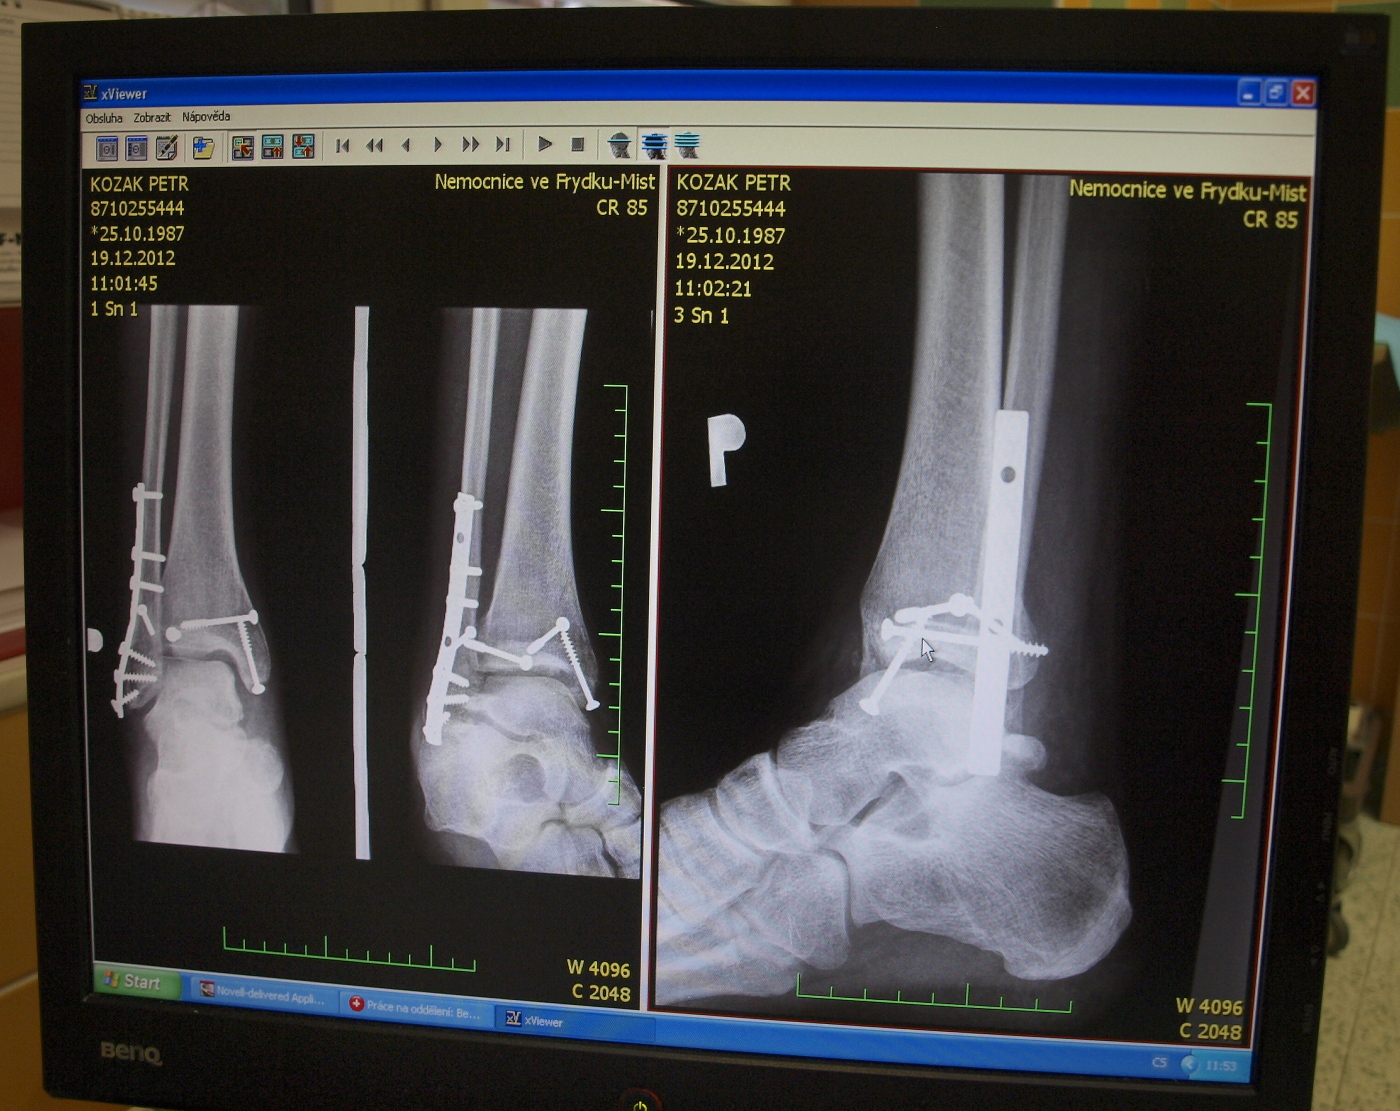

Petis píše:Takže situace je taková, že veškeré práce, které byly v plánu přes zimu se musí odložit na neurčito. Důvod je mnohonásobná zlomenina kotníku + přetrhané všechny vazy. Takže mám v pravém kotníku x šroubů + nějakou výztuž. Léčba odhadem na 4-5 měsíců. Honda je momentálně zazimována na baráku u rodičů. ...tak to dopadá když se někdo rozhodne, že bude přes zimu sportovat :D

Vypadá to asi nějak takhle, ale prý se to hojí víc než dobře, tak snad budu co nejdřív normálně chodit.